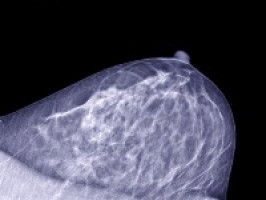

Las virtudes de amamantar al bebé alcanzan al cáncer. En 2011, un trabajo de la Universidad de Granada observó que las mujeres que dan el pecho a sus hijos durante más de seis meses tienen menos posibilidades de padecer cáncer de mama. Ahora, una nueva investigación va aún más allá y cuantifica que la lactancia materna podría reducir el riesgo de la madre de contraer cáncer de mama hasta en 20 por ciento.

Según cuenta en Reino Unido el diario The Telegraph, la investigación ha encontrado que dar el pecho no solo protege contra los tipos comunes de cáncer de mama, sino contra el cáncer triple negativo, uno de los más difíciles de tratar.

El estudio, dirigido por la Escuela de Medicina y el Hospital Mount Sinai de Nueva York y la Universidad de Washington, junto a asociaciones de cáncer de Norteamérica, examinó datos sobre más de 750 mil mujeres en cuatro continentes a lo largo de unos 30 años.

El trabajo, que se presenta en el San Antonio Breast Cancer Symposium, celebrado en EE UU, muestra que dar el pecho al bebé tiene un efecto significativo sobre el riesgo de la madre a contraer cáncer de mama.

“La lactancia materna es una estrategia poderosa para reducir el riesgo de varios subtipos de cáncer de mama agresivos, con una reducción del riesgo relativo de entre 10 y 20 por ciento”, dice el estudio.